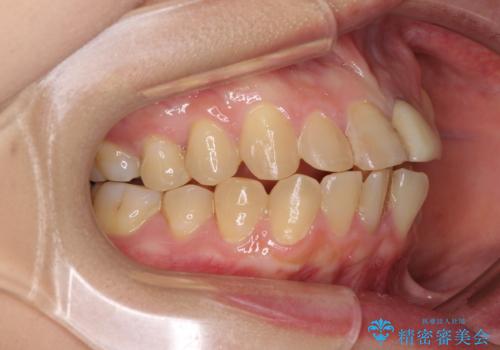

- 前歯のデコボコと変色した前歯を気にして来院された患者様です。

抜歯矯正により口元を引っ込めることも検討しましたが、特に口元の突出感は気になっていないとのことで、非抜歯にてワイヤー装置で矯正治療を行うこととしました。

舌の突出癖により治療期間中に開咬となり、治療が長引きましたが、口元も治療前よりも引っ込めることができ、すっきりとした仕上がりとなりました。